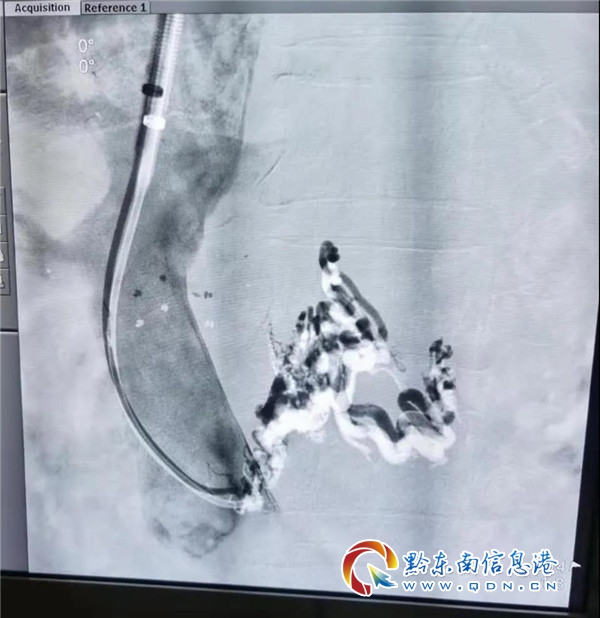

2020年5月24日星期天早上11點,在貴醫大介入科許敏博士、州醫院放射科唐昌連、王芳清主任指導下,配合麻醉科的精湛技術,細致消毒鋪巾后,放射科介入團隊在介入室細心操作。兩小時后,這場高難度、高強度的TIPS手術終于完美結束,肝內門-腔靜脈支架順利置入,食道-胃冠狀靜脈完美栓塞,經術后3天觀察,患者無不適癥狀,各項生理指標較前有改善。

TIPS(經靜脈肝內門體靜脈分流術)是治療門靜脈高壓癥的有效介入新技術,目前屬于介入學界頂尖技術之一,其中分流部位位置的選擇、穿刺及支架的置入等都需進行精確判斷、操作,該手術目前在國內只有部分省級以上大醫院能夠完成。TIPS手術在DSA透視引導下,采用導絲導管技術,在門靜脈與肝靜脈之間置入內支架,建立一個分流通道,達到降低門靜脈壓力,從根本上控制肝硬化失代償期上消化道大出血的頑疾,同時還可以對已經曲張的食道和胃底靜脈進行栓塞,進一步增強止血效果。該手術對減少腹水也有較理想的效果。